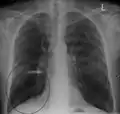

A chest X-ray is not useful to establish a diagnosis of COPD but it is of use in either excluding other conditions or including comorbidities such as pulmonary fibrosis and bronchiectasis. Characteristic signs of COPD on X-ray include hyperinflation (shown by a flattened diaphragm and an increased retrosternal air space) and lung hyperlucency.[5] A saber-sheath trachea may also be shown that is indicative of COPD.[111]